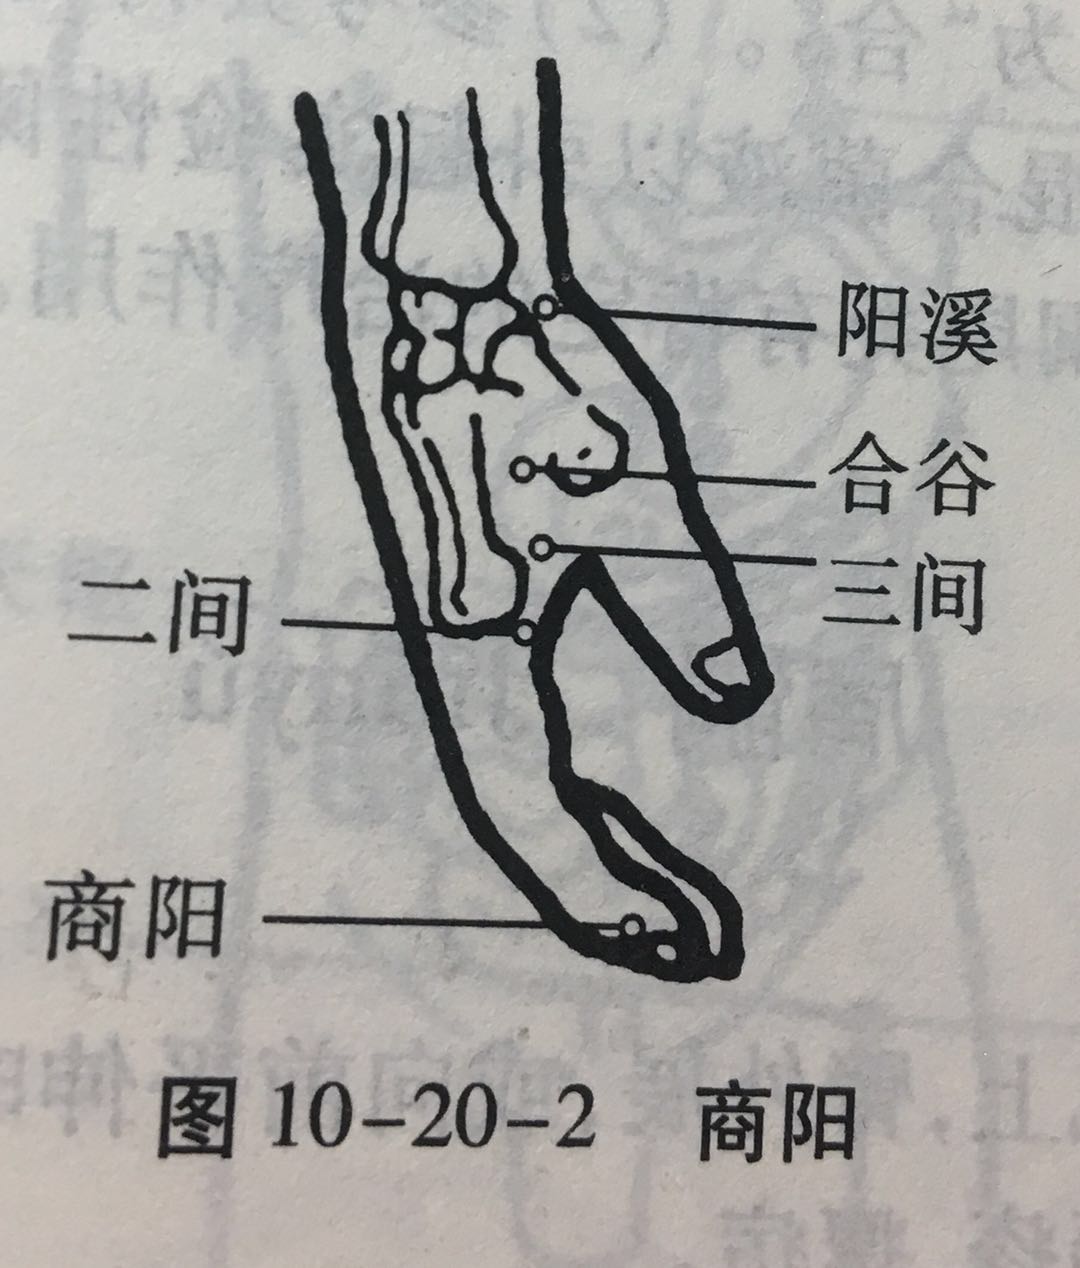

商阳

【定位】 在手食指末节桡侧,距指甲角 0.1 寸(图 10-20-2)。

【主治】 耳聋,齿痛,咽喉肿痛,颌(hé)肿,青盲,手指麻木,热病,昏迷。

【配伍】 配少商点刺出血治热病、昏迷。

【刺灸法】 浅刺 0.1 寸,或点刺出血。

【附注】 手阳明经所出为“井”。

合谷

【定位】 在手背,第1、2掌骨间,当第 2 掌骨桡侧的中心点(图 10-20-2)。

简便取穴:以一手的拇指指骨关节横纹,放在另一手拇、食指之间的指蹼缘上,当拇指尖下是穴。